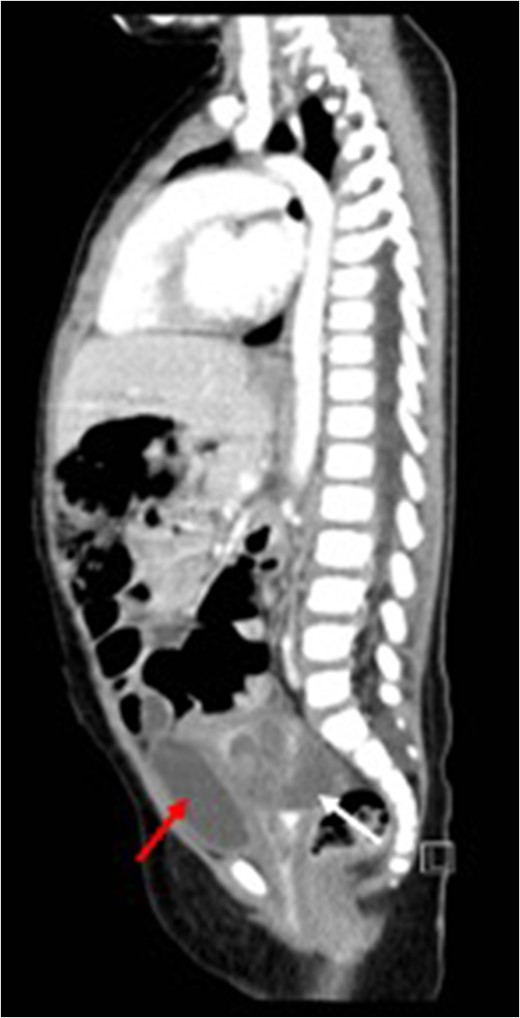

Post-treatment sagittal view (CT) with no evidence of recurrence arising from the uterus (red arrow) bladder.